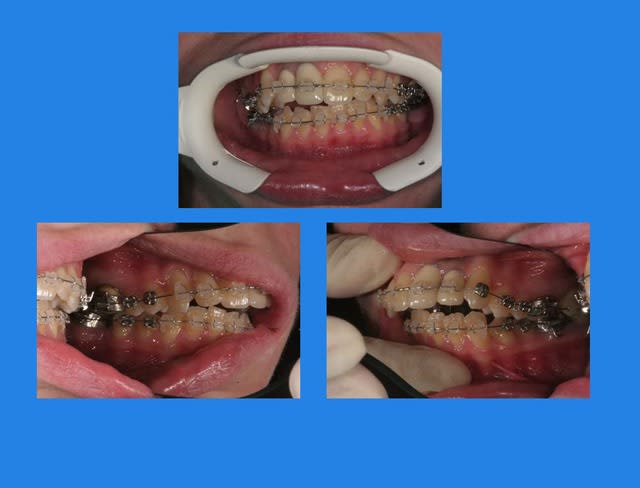

Cas présenté :

Sexe : XX

Age 24 ans

m’a été envoyé en Ortho

Motivation : voudrait arranger son sourire ( 11-21),

Voici les Rx. de début

Tu n'as jamais présenté un cas complet dans ta vie ou quoi ? Avec des photos face et profil + photos des arcades et photos des moulages, et forcément les radios ?

Début du cas :

pose mat Sup.